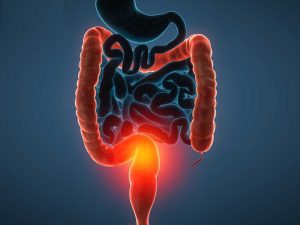

خون در مدفوع یکی از نشانههای نگرانکنندهای است که میتواند از مشکلات سادهای مانند هموروئید یا شرایط پیچیدهتری مانند سرطان روده بزرگ ناشی شود. مشاهده خون در مدفوع، به ویژه اگر به صورت مکرر اتفاق بیفتد، نیازمند توجه فوری پزشکی است. این علامت ممکن است ناشی از مشکلات مختلفی در دستگاه گوارش باشد که هر کدام نیازمند درمان خاص خود هستند. در این مقاله، به بررسی علل شایع خون در مدفوع، علائم همراه، روشهای تشخیص، و روشهای درمانی پرداخته میشود. همچنین بهترین پزشکان متخصص گوارش و کبد در تهران برای درمان این مشکل معرفی خواهند شد. علل خون در مدفوع هموروئید: یکی از شایعترین علل خون در مدفوع، هموروئید یا